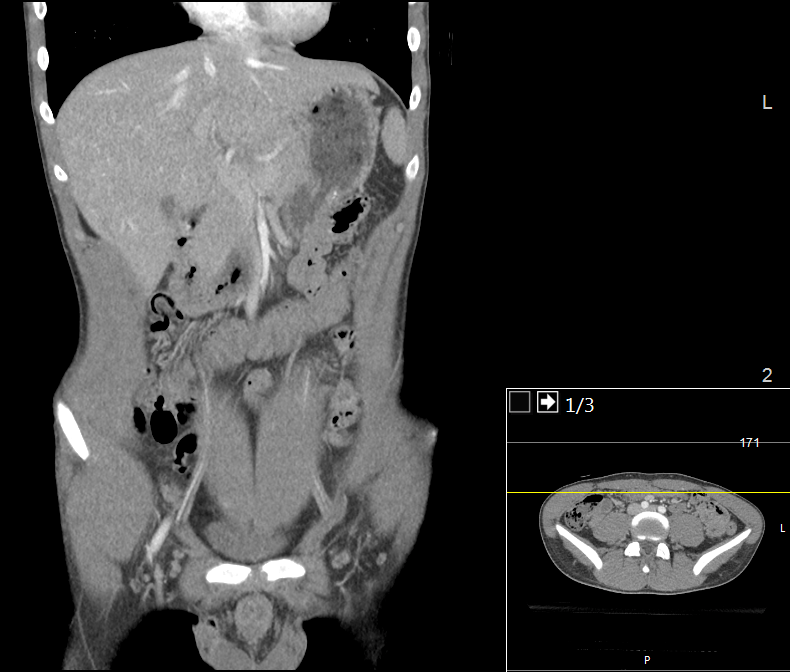

The Computer Tomography (CT) scan represents a widely used and valuable imaging diagnostic tool in modern medicine. It enables medical professionals to detect the presence of tumors, traumatic injuries, hemorrhages, and a range of other health abnormalities (Computed Tomography (CT), 2022).

The technique uses a rotating X-ray beam around the patient to generate cross-sectional images, which are then processed and subsequently stacked to create a 3D image. However, the procedure requires exposure to ionizing radiation, which poses a potential threat to DNA. Ionizing radiation can lead to single-stranded and double-stranded DNA breakages, which may lead to mutations and, ultimately, to cancer. Although the radiation doses used in CT scan procedures are considered generally safe, concerns have been raised regarding children, who are more susceptible to the harmful effects of ionizing radiation, as well as those patients who undergo repeated exposures.